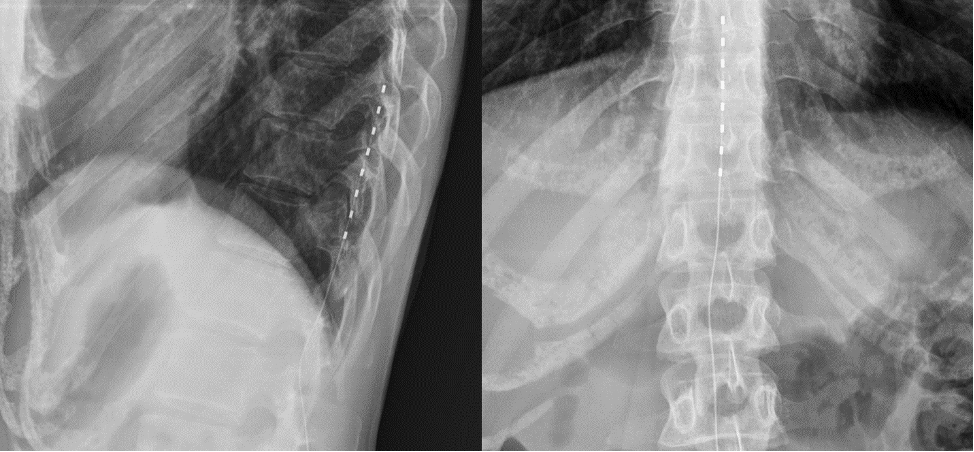

Пациентка С., 32 лет, перенесла хирургическое удаление подкожной липомы, локализованной на дорсолатеральной поверхности левой стопы, кзади латеральной лодыжки. В раннем послеоперационном периоде манифестировал выраженный болевой синдром жгучего характера с иррадиацией по латеральной поверхности стопы, сопровождавшийся парестезиями и гипестезией пальцев. Интенсивность боли по визуальной аналоговой шкале (ВАШ) достигала 8 баллов. Неврологическое обследование и инструментальная диагностика подтвердили ятрогенное повреждение n. suralis в зоне операционного доступа. Последовательные попытки хирургической коррекции (иссечение краевой невромы) и консервативной терапии (габапентин 900 мг/сут, дулоксетин 60 мг/сут, венлафаксин 150 мг/сут) оказались неэффективными: отмечался кратковременный анальгетический эффект с последующим рецидивом боли до следующего приёма препаратов.В 2022 г. пациентке выполнена имплантация системы для хронической SCS на уровне Th10–Th12 (см.рис.1). Парестезии от стимуляции охватывали область боли на 80% и снижали выраженность болевого синдрома на 30%.

Рисунок 1. Рентгенологическая картина имплантированного электрода в заднее эпидуральное пространнство на уровне Th10-Th12 позвонков.